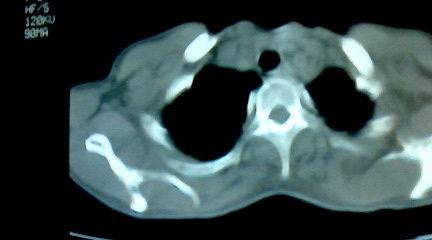

标题: CT25218:请教!胸部CT,胸8椎体骨质破坏,伴周围软组织肿。 [打印本页]

标题: CT25218:请教!胸部CT,胸8椎体骨质破坏,伴周围软组织肿。

患者,女41岁,肢体乏力。

两肺上叶继发性肺结核;胸椎结核并椎旁寒性脓肿形成。

胸椎结核并椎旁寒性脓肿形成。